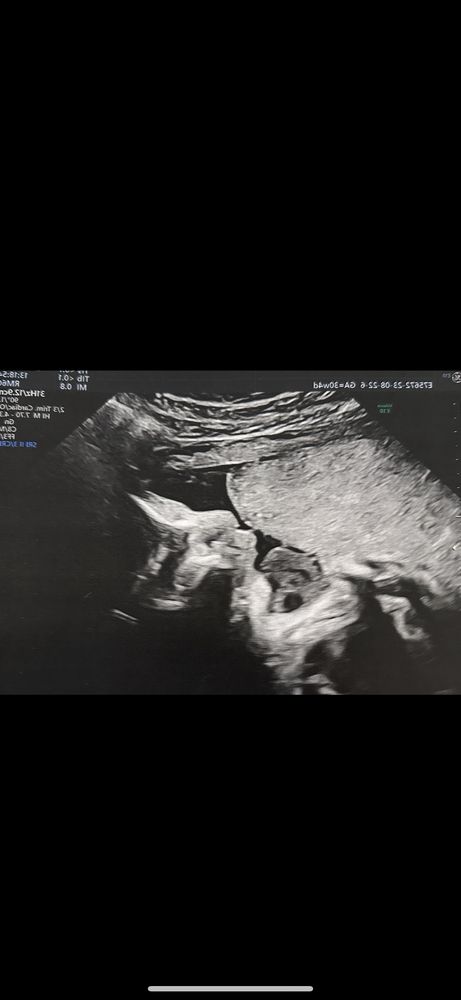

такая история, у меня сейчас 31 Нед,вчера была на скрининге последнем☺️ с малышкой все хорошо слава богу, потом отдали фотографии с узи,не могу понять, то ли я выдумываю,то ли подбородочек ну слишком маленький) нормально ли это вообще ,у кого так было ? Начиталась про микрогению и немного запереживала,хотя врач не говорил ничего про это.. прикреплю две фотки ,одну на 27 нед,другая 31 нед

на втором фото видно, что губы трубочкой сложила, поэтому кажется что меньше.

очень красивый и аккуратный подбородок 😍

An9999999, ой да от мужа только подбородок как раз у него он маленький и аккуратный 😂 так что не наводим панику , в обычном узи и 3д узи есть отличие ( в обычном -носик маленький был , а вот в 3Д- носик кортошка как у меня 😂) так что не переживайте все хорошо с вашим подбородком просто он так сейчас выглядит миниатюра 😍😍😍

Обычный подбородок

у нас ещё меньше был на снимке , после рождения очень красивый милый подбородочек у нас))

Обычный подбородок у малышки, вы себе просто уже рисуете страшные картинки, так как вышли на финишную прямую и роды не за горами, волнения по каждому поводу настигают. Я сама сейчас такая же, даже сны дурные сниться начали😄